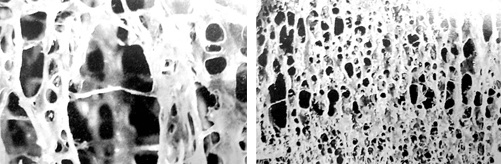

3. 골다공증예방

삼채는 뼈와 연골을 튼튼하게, 골밀도를 강화시켜 골다공증을 예방하는데도 이로운 작용을 한다고 합니다. 또한 삼채는 요산을 배출시키는데도 이로운 작용을 하여 통풍 예방에도 도움을 준다고 합니다.